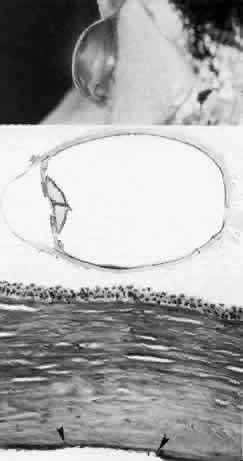

Congenital Central Corneal Opacity (Peters' Anomaly)

Peters' anomaly is a congenital, central corneal opacity with corresponding defects in the posterior stroma, Descemet's membrane, and endothelium (Fig. 3).16,23,34,35 Most cases of Peters' anomaly are sporadic, although both recessive and irregular dominant inheritances have been described. Eighty percent of reported cases are bilateral.

Fig. 3. Peters' anomaly. Schematic drawing of ocular features. Top left. Clinical photo of typical bilateral Peters' anomaly with large, dense central leukomata, which was successfully treated by penetrating keratoplasty with optical iridectomy of the fellow eye. Top center. Intraoperative photo demonstrates adhesion of the lens to the posterior cornea as a corneal button (grasped with forceps) is trephined. Top right. Successful penetrating keratoplasty of a patient with bilateral Peters' anomaly. Bottom, upper left. Survey light photomicrograph of a corneal button from the case illustrated clinically (top center) shows termination of Bowman's membrane (at arrowhead) corresponding to the area of adhesion between the posterior cornea and lens (L). Descemet's membrane, present peripherally, terminates centrally in a layer of retrocorneal fibrous tissue (*) interposed between the lens and stroma. Direct contact between the retrocorneal fibrous tissue and continuous lens capsule is evident (paraphenylenediamine, phase contrast, × 60). Bottom, lower left. Phase-contrast micrograph of posterior cornea adjacent to a central stromal defect shows termination (at arrowhead) of undulating Descemet's membrane between the stroma and retrocorneal fibrous tissue (paraphenylenediamine, × 400). Bottom right. Transmission electron micrograph of posterior cornea shows attenuated keratocytes (K) with phagocytic contents, disorganized posterior stromal lamellae, and markedly thin and multilaminar Descemet's membrane (DM) with attenuated but continuous endothelium (E). AC, anterior chamber. (x 7000) (Schematic. Grayson M: Diseases of the Cornea, p 29. St. Louis, CV Mosby, 1979)

Although Peters' anomaly is, in general, characterized by a central corneal leukoma, two clinical variants have been recognized (Color Plate 1B).36

Peters' anomaly type I shows the typical nebular opacity in the pupillary axis, bordered by iris strands that cross the anterior chamber from the iris collarette. The lens usually remains clear and is normally positioned. Associated anomalies such as microcornea, sclerocornea, and infantile glaucoma may be present, but, for the most part, no other ocular or systemic abnormalities are present.

In Peters' anomaly type II, in contrast, the lens is abnormal either in position or transparency in addition to the central corneal opacity and iridocorneal synechiae. Centrally, the posterior cornea and lens may be adherent, and there may be an anterior polar cataract. This type is more frequently bilateral and almost every involved case shows severe ocular and systemic malformations.37 In general, 50% to 70% of cases of Peters' anomaly have concomitant glaucoma. Other associated abnormalities of the anterior segment include microcornea, microphthalmos, cornea plana, sclerocornea, colobomas, aniridia, and dysgenesis of the angle and iris.

Histopathologic changes are present in all layers of the cornea in Peters' anomaly.19,20,38–41 Often the anterior changes, which include disorganization of epithelium, fibrovascular pannus, and loss of Bowman's layer due to long-standing edema, are secondary to the posterior abnormalities. Fluid lakes are also present in the affected stroma.

In the peripheral and unaffected areas, the corneal endothelium forms a continuous monolayer, and Descemet's membrane is of normal, uniform thickness (approximately 5μm). In the area of defect, however, endothelium and Descemet's membrane can terminate abruptly or be severely attenuated. The affected Descemet's membrane is composed of multiple laminations of basement membrane-like material, with interspersed collagen fibrils and fine filaments. Since such abnormal material is elaborated by the corneal endothelium, a fibroblastic metaplasia of the endotheliogenic mesenchyme is likely, as is thought to occur in a number of corneal conditions in which the endothelium is similarly disturbed to secrete a posterior collagen layer.42,43

The lens abnormalities in Peters' anomaly are characterized histologically by a stalklike connection between the lens and the posterior corneal defect, suggesting primary incomplete separation of the lens vesicle. Alternatively, there may be contact of a morphologically intact lens to the posterior cornea, suggesting subsequent anterior displacement of a normally developed lens.

There are several reasonable explanations for a central corneal leukoma of the Peters' variety. One is incomplete central migration of corneogenic mesenchyme (i.e., neural crest cells), accounting for posterior endothelial and stromal defects.23 This is corroborated by the finding of abnormally large stromal collagen fibrils of 36 to 60 nm in some patients with Peters' anomaly. A similar abnormality of mesenchymal development is found also in sclerocornea and congenital hereditary endothelial dystrophy.22 Another explanation of posterior corneal leukoma of a Peters' type is an in utero subluxation of the lens, either prior to or after its full development, in either case interrupting the normal migration or function of the developing endothelium.